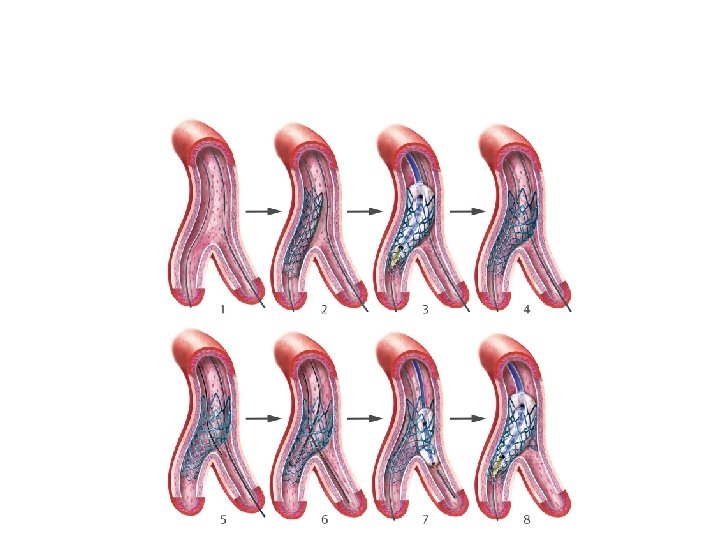

Culotte technique

� It provides near-perfect coverageof the carina &SBostium atthe expense of an excessof metal covering in proximal. MB. � Bestimmediate angiographic result &theoretically itmayguarantee a more homogeneous distribution of struts &drug. � Canbeused in all bifurcation lesions irrespective of bifurcationangle. � Open-cell stents arepreferred when the SBdiameter is >3 mm. � Disadvantages – � Complexity in the rewiring of both branches through the stentstruts, � Not advisable if both branches aredissected afterpredilatation.